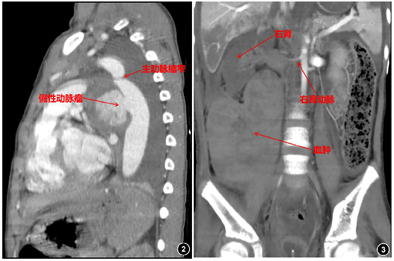

入院后予万古霉素、美罗培南抗感染及支持对症治疗,仍有发热,体温波动于38℃左右,于住院第5天偶诉胸痛、胸闷,可耐受,可自行缓解,复查心脏超声:肺动脉分叉处与降主动脉间见一囊实性回声包块,显示范围约74.8 mm×55.9 mm,内为等回声及无回声。于住院第6天胸痛、胸闷症状加重,伴多汗,每次持续1~20 min不等,前倾位稍缓解,伴呼吸、心率增快,发作时监测血压明显增高,收缩压最高达170 mmHg,含服硝苯地平后可暂时缓解。查体:精神反应欠佳,面色稍苍白,呼吸频率33次/分,三凹征阴性,双肺呼吸音粗,左肺呼吸音减低,可闻及少许痰鸣音,心率101次/分,心音有力,律齐,腋前线第4肋间可闻及2/6级收缩期杂音,足背动脉搏动弱,余未见明显阳性体征。行纵隔增强CT(图2):降主动脉起始段明显缩窄,直径约2.3 mm,狭窄段远端约17 mm处可见降主动脉前缘一膨大造影剂影突出腔外,最大截面约4 5mm×31 mm,上下长度约32 mm,主动脉裂口处宽度约19.4 mm,突出部分周围可见环状软组织密度影包绕,考虑假性动脉瘤形成;复查血常规:WBC 16.17×109/L,Hb 92 g/L,HCT 28.20%,Plt 357×109/L,N 87.0%,L 8.2%,CRP 69.11 mg/L。完善术前检查,于住院第9天全麻低温体外循环下行降主动脉瘤切除、主动脉缩窄切除、人工血管置换术、肺脓肿引流术。术中探查见主动脉峡部缩窄,内径0.3 cm,长约1.2 cm,缩窄段以远2.0 cm处起始主动脉破口,长约3.0 cm,横径1.5 cm,瘤体深入至左肺叶内,5.0 cm×6.0 cm×6.0 cm大小,左肺整体不张实变,张力较高。术中诊断:主动脉缩窄、降主动脉假性动脉瘤、感染性心内膜炎、肺炎并肺脓肿。病理检查示:壁内纤维组织增生及片状出血伴炎症反应,符合假性动脉瘤。术后呼吸机辅助通气,继续予美罗培南+万古霉素抗感染、硝普钠控制血压,体温正常,病情逐渐恢复。于住院第18天,患儿偶诉腹痛,可自行缓解,伴有低热,37.4℃,当天夜间,患儿突然腹痛加重,伴面色苍白、烦躁、意识淡漠。体格检查:T 37.4℃,P 120次/min,R 40次/min,BP右上肢110/65 mmHg。意识模糊,面色及口唇苍白,颈软,无抵抗,呼吸稍促,三凹征阴性,双肺呼吸音粗,未闻及明显湿啰音,心率120次/min,心音有力,律齐。腹韧,右下腹压痛、反跳痛及肌紧张,肝脾肋下未触及,肠鸣音正常,四肢末梢凉,CRT 4 s。急查腹部超声示:右腹部异常回声包块(血肿形成?),急诊腹部增强CT(图3):右肾动脉近段纤细,远端未见显示,右肾实质内可见数条纤细较淡造影剂血管影走行,右肾静脉未见明确显示。右肾受压右移,其内侧及下缘周围可见大片状不均质密度影,大小约90 mm×88 mm×121 mm,内部密度不均,未见明显强化,考虑为巨大血肿。立即全麻下行多学科联合手术(心内科、心外科、普外科、泌尿外科),行腹主动脉造影+肾动脉球囊扩张术+单侧肾切除术+腹膜后血肿清除术。行腹主动脉造影示右肾动脉造影剂外溢。右腹部脐上2 cm长约18 cm横切口,依次打开皮下、腹直肌、腹膜,见腹腔大量凝血块、不凝积血,右下腹膜外巨大血肿,肝脏受压,肠道移向右腹部,右肾呈暗红色,已失活,肾动脉不规则破裂达2/3直径。球囊充液扩张阻断腹主动脉近右肾动脉开口处血流(图4)。清除腹腔及腹膜外凝血块、积血等,暴露肾蒂,游离右肾动静脉、输尿管,7#丝线分别双重结扎、切断右肾动静脉,回抽球囊开放血流,未见出血。同时结扎、切断右侧输尿管,取出失活右肾(图4),充分止血,盐水2000 ml冲洗腹腔。术中诊断:肾动脉破裂;腹膜后血肿。病理诊断:右侧肾脏广泛出血、坏死(图5)。术后体温不稳定,血压仍高,且转氨酶逐渐升高,于住院第33天将万古霉素更换为利奈唑胺(斯沃),后体温逐渐正常,于住院第63天将抗生素降级为舒普深,3 d后停抗生素,观察2 d无症状,临床治愈,于2018年6月29日出院。

根据药敏试验积极抗感染治疗,心外科全麻低温体外循环下行降主动脉瘤切除、主动脉缩窄切除、人工血管置换术、肺脓肿引流术。术后9 d出现腹痛,腹部超声及CT提示巨大血肿,心内科行腹主动脉造影明确部位后给予球囊充液扩张阻断腹主动脉近肾动脉开口处血流,普外科及泌尿外科联合立即行腹膜后血肿清除术及单侧肾切除术,术后继续抗感染及降压治疗。